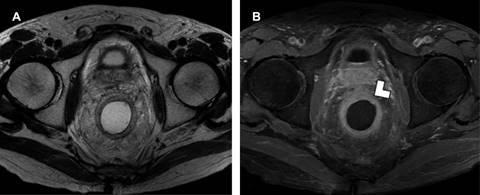

Figura 1: A) Resonancia magnética (RM) de recto en secuencia T2 con gel endorrectal, muestra tumor circunferencial del recto inferior, que no involucra la muscular propia. B) Mismo paciente, RM en secuencia T1 con saturación grasa y gadolinio muestra infiltración del tumor que involucra la muscular propia y la grasa mesorrectal (punta de flecha).